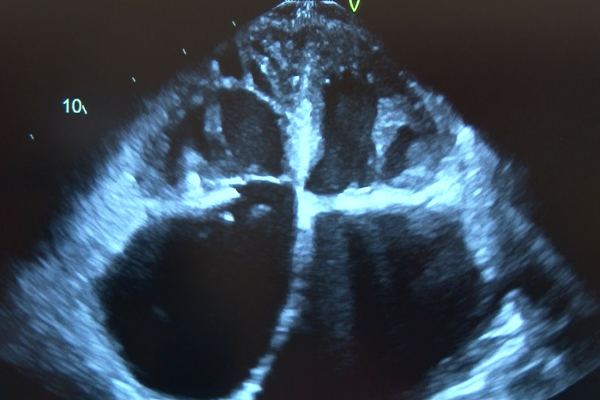

To this end, the updated document incorporates a new algorithm based on only four variables to diagnose the presence or absence of diastolic dysfunction, and also offers a new algorithm to estimate LV filling pressures with fewer variables than the 2009 guidelines. The approach is similar for patients with both depressed and normal ejection fractions. The grading of diastolic dysfunction is linked to estimation of LV filling pressures, and a single algorithm is used for both.